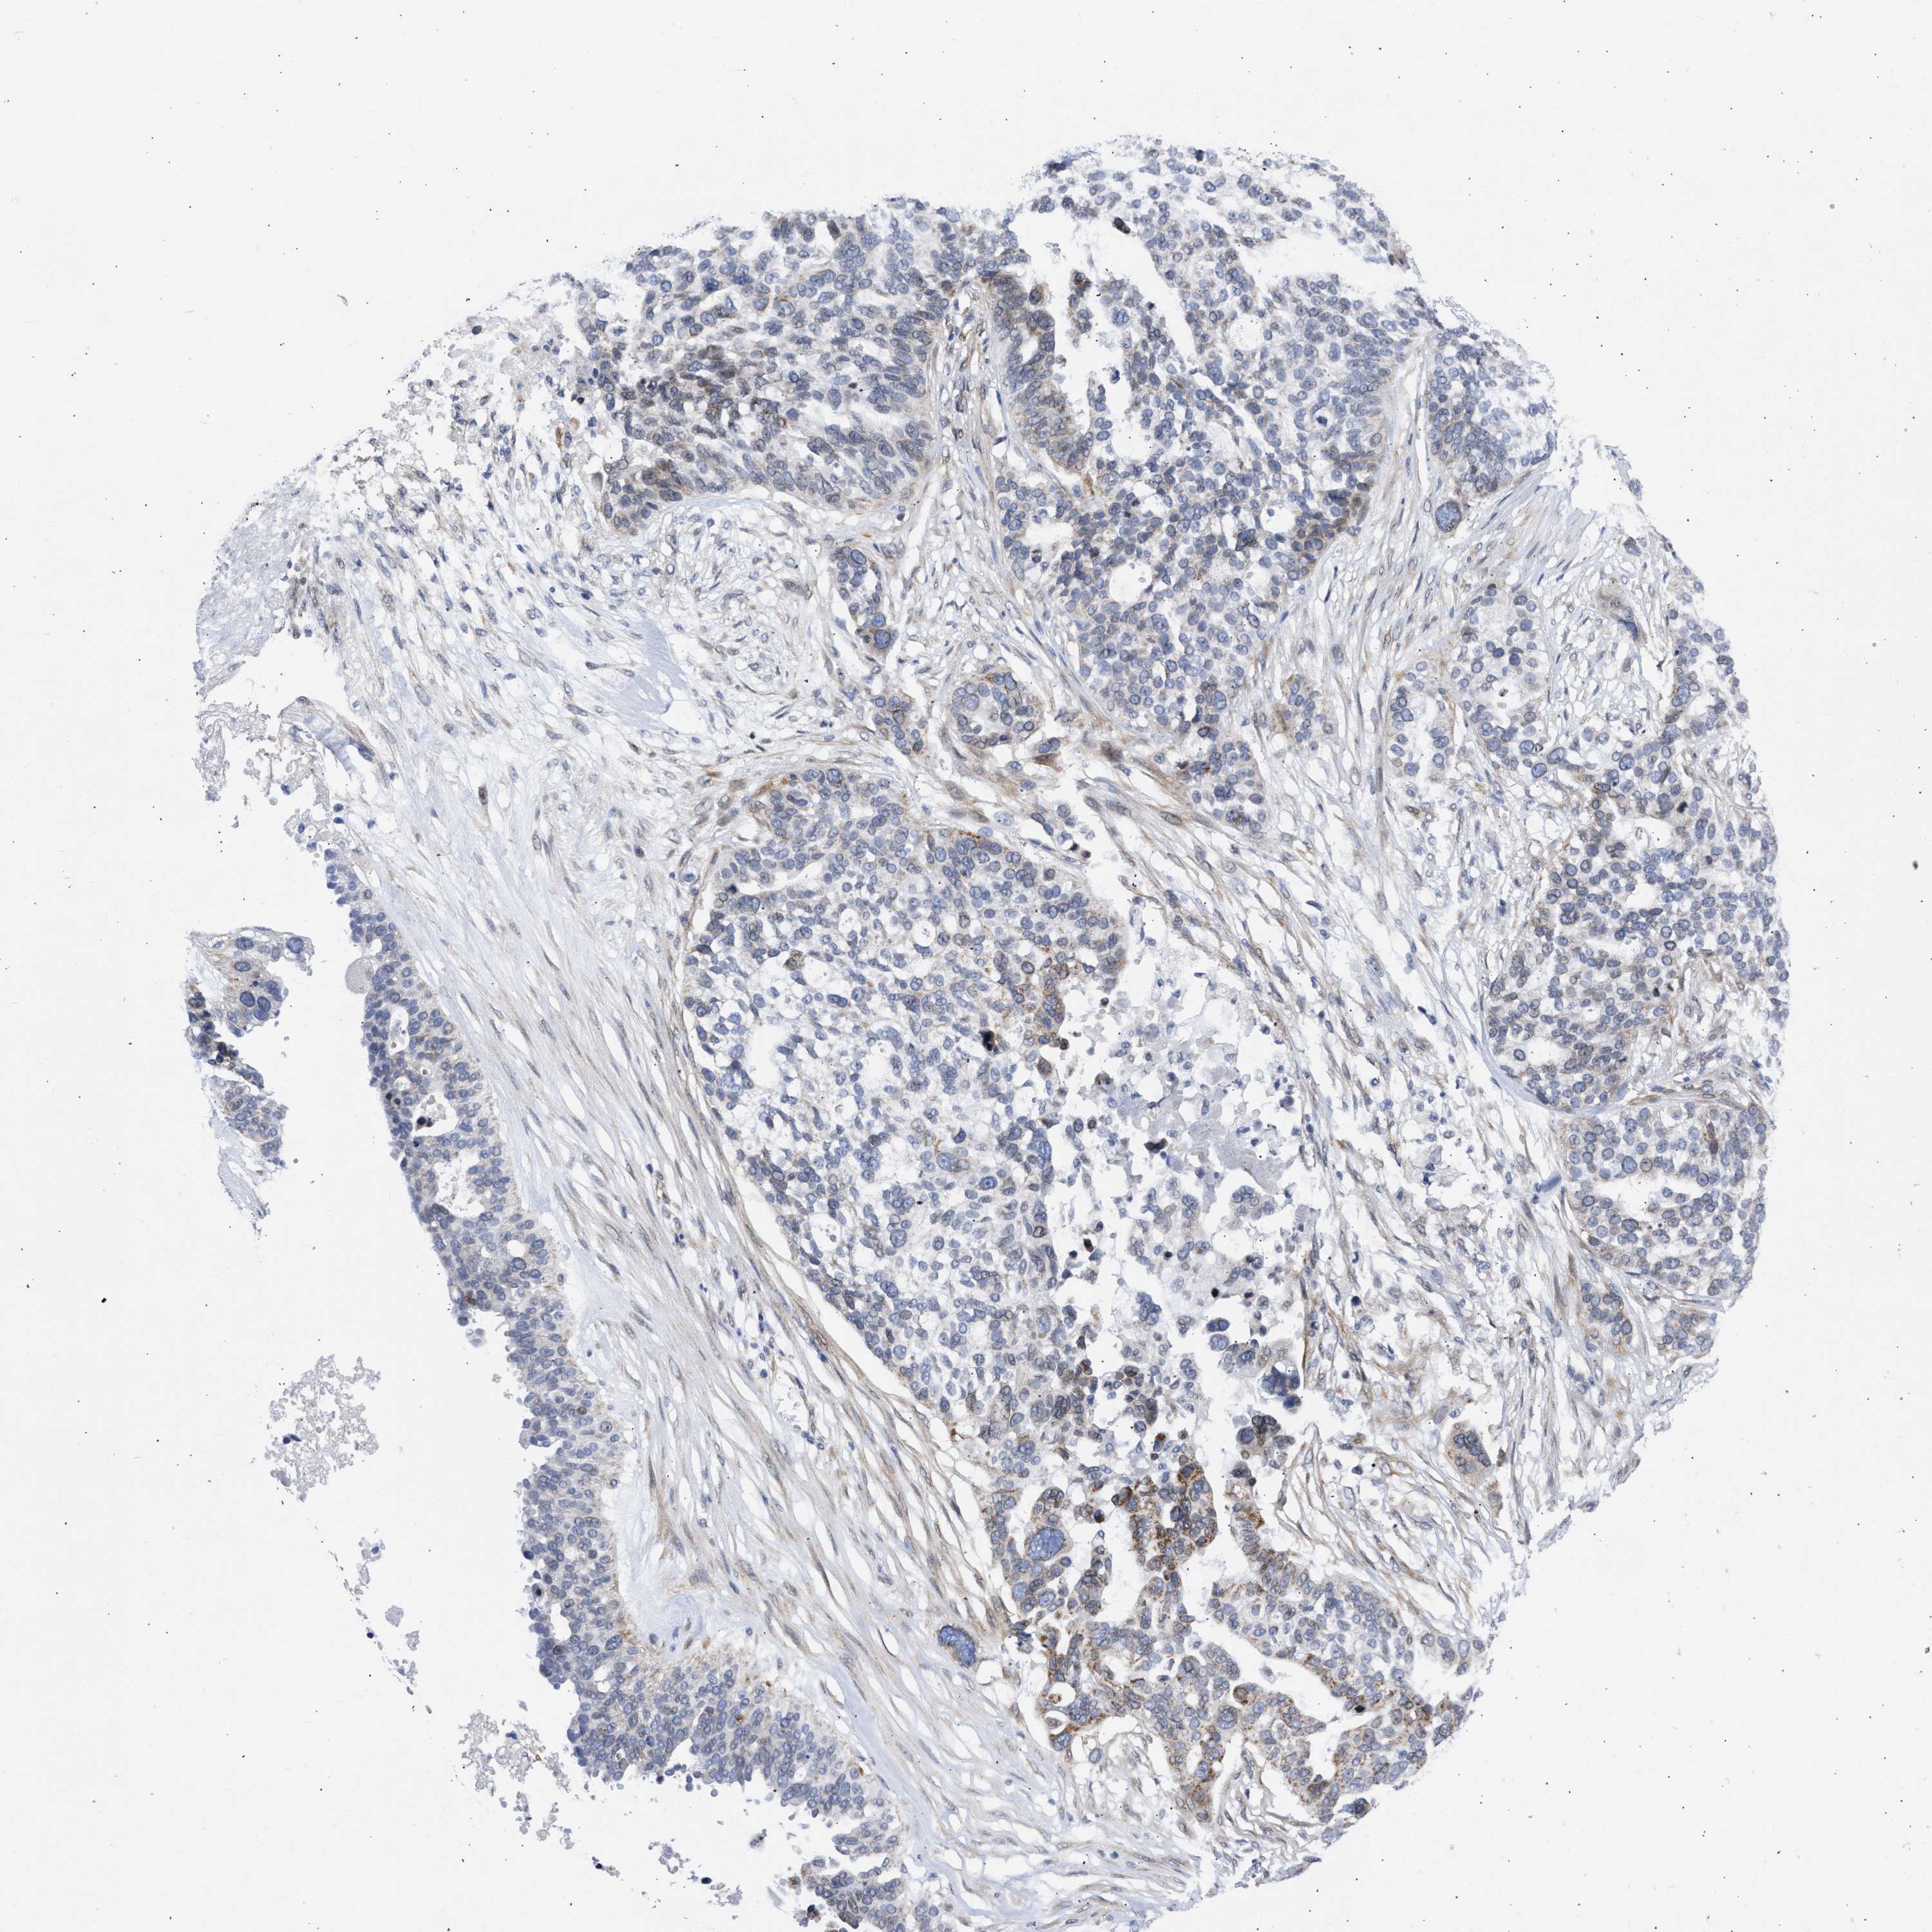

OVARIAN CANCER - Protein expressioni

A mouse-over function shows sample information and annotation data. Click on an image to view it in a full screen mode. Samples can be filtered based on level of antibody staining by selecting one or several of the following categories: high, medium, low and not detected. The assay and annotation is described here.

Note that samples used for immunohistochemistry by the Human Protein Atlas do not correspond to samples in the TCGA dataset.

Antibody stainingi

Antibody staining in the annotated cell types in the current human tissue is reported as not detected, low, medium, or high, based on conventional immunohistochemistry profiling in selected tissues. This score is based on the combination of the staining intensity and fraction of stained cells.

Each image is clickable and will lead to virtual microscopy that enables deeper exploration of all samples and also displays staining intensity scores, fraction scores and subcellular localization as well as patient and tissue information for each sample.

Antibody HPA018401

Carcinoma, endometroid